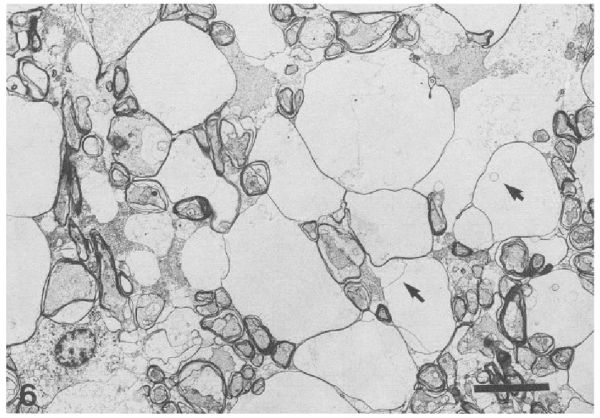

最惊人的发现,藏在白头海雕的大脑中——所有死亡的白头海雕,其脑髓白质中都出现了大大小小的圆形小泡,有的独立出现,有的则是像一串葡萄一样串联在一起。这些泡泡多数是中空状态,极少数能观察到里面残留的膜结构碎片。

箭头所示为脑髓中出现的空洞 | 参考资料[2]

这是一种从未出现过的奇怪的大脑病症,科学家后来将其命名为“空泡性髓鞘病”(Vacuolar Myelinopathy)。从那些出现了病例的水库中,研究者回收了沉积物和死鸟尸体,进行了初步化学分析。结果却发现,当时已知的会诱发哺乳动物和鸟类类似疾病的化合物,例如六氯酚、三乙基锡或溴甲苄灵,都未能在这些样本中被检测到。